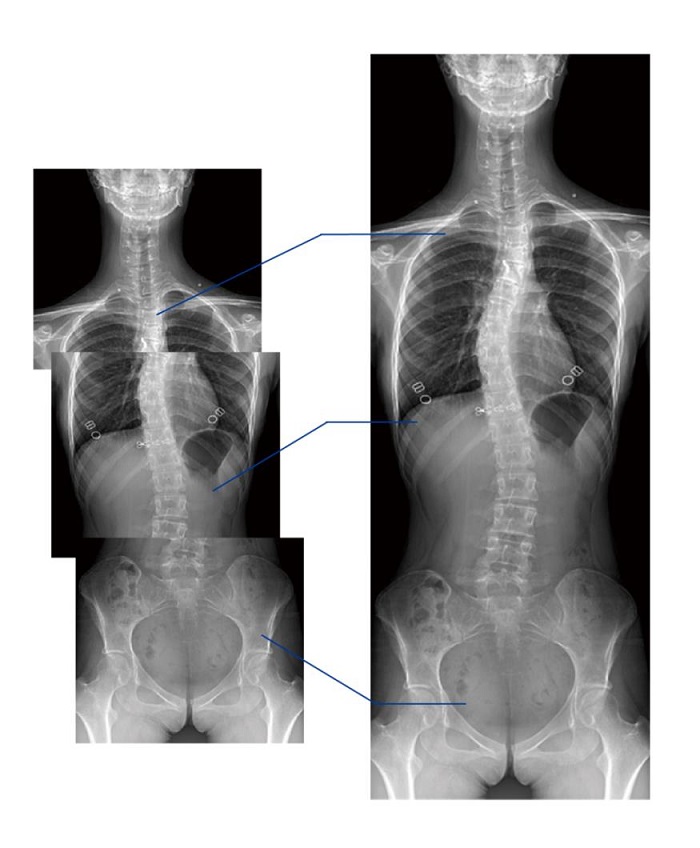

另外,動態(tài)DR的全景拼接功能,可通過對脊柱、下肢及下肢靜脈造影進(jìn)行分段攝片,然后對分段圖像進(jìn)行拼接,在一幅X光圖像上完整顯示全脊柱或下肢整體形態(tài)。對于骨科疾病患者的全脊柱、全下肢病變情況圖像展示更加具有完整性,有助于骨科疾病患者臨床診斷效果的提升。

普利德多功能動態(tài)DR將數(shù)字?jǐn)z影、數(shù)字透視、數(shù)字造影、毫秒級高清點(diǎn)片、影像實(shí)時保存與回放、全景拼接等多種功能集于一身。像素尺寸達(dá)到業(yè)界領(lǐng)先的100微米,率先實(shí)現(xiàn)5.0lp/mm超高分辨率成像,大幅提升細(xì)節(jié)檢測能力;透視幀率高達(dá)30幀/秒,有效避免漏診、誤診;靜態(tài)攝影有效像素高達(dá)1800萬,較之于傳統(tǒng)900萬點(diǎn)片像素,圖像細(xì)節(jié)更加清晰銳利,影像質(zhì)量躍升至新高度,為隱匿性肋骨骨折診斷提供至清影像,輔助醫(yī)生實(shí)現(xiàn)精準(zhǔn)診療!